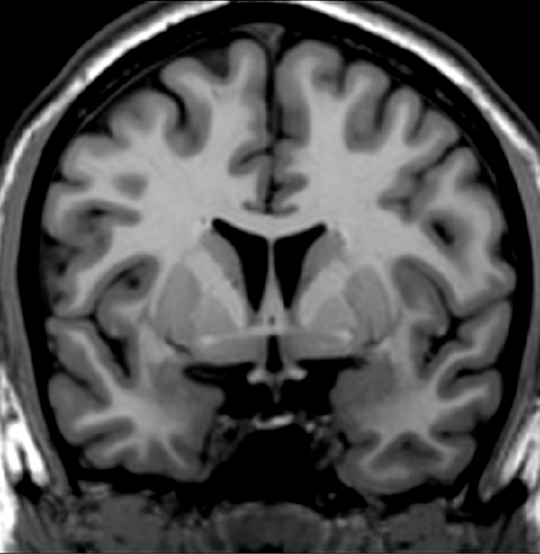

Locate a bundle of fibers that interconnects the temporal lobes.